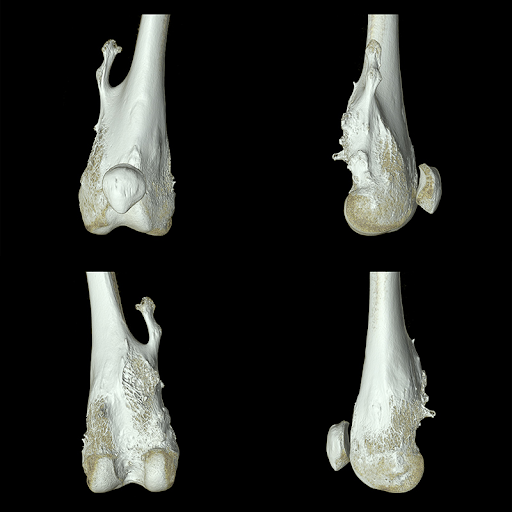

Визуализация опорно-двигательного аппарата